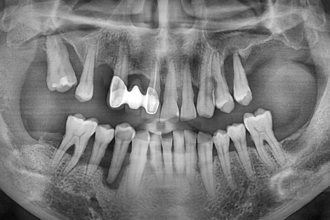

임플란트